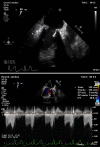

Patients with COVID-19 may present a hypercoagulable state, with an important impact on morbidity and mortality. Because of this situation pulmonary embolism is a frequent complication during the course of infection. We present the case of a patient recently discharged, after admission with confirmed COVID-19, who developed a pulmonary embolism and thrombosis of a biological mitral valve prosthesis, producing valve obstruction and stenosis. After 15 days of anticoagulant treatment, resolution of the thrombus and normalisation of prosthetic valve function was observed. This case supports current recommendations of administering full-dose anticoagulation therapy to COVID-19 patients with biological heart valve prosthesis, even after the acute phase of infection.